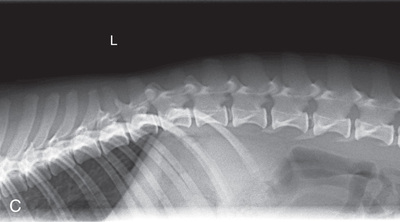

High-quality images are needed to see subtle changes in bone opacity, shape, and angulation of the vertebrae or vertebral column1,2 (Table 20.1). The common views of this portion of the axial skeleton are the lateral (L) and ventrodorsal (VD) views of the cervical, thoracic, thoracolumbar, lumbar, lumbosacral, sacral, and caudal vertebrae. Depending on the size of the patient, a full survey study is either four or five images of each orthogonal view.

MEASURE: Level of L1.

CENTRAL RAY: L3 to L4 (palpate).

BORDERS: T12 to S1 (Just cranial to origin of last rib to just before the greater trochanter).

CENTRAL RAY: Level of L4 (palpate).

BORDERS: T12 to S1 (Just cranial to both the origin of the last rib and acetabulum).